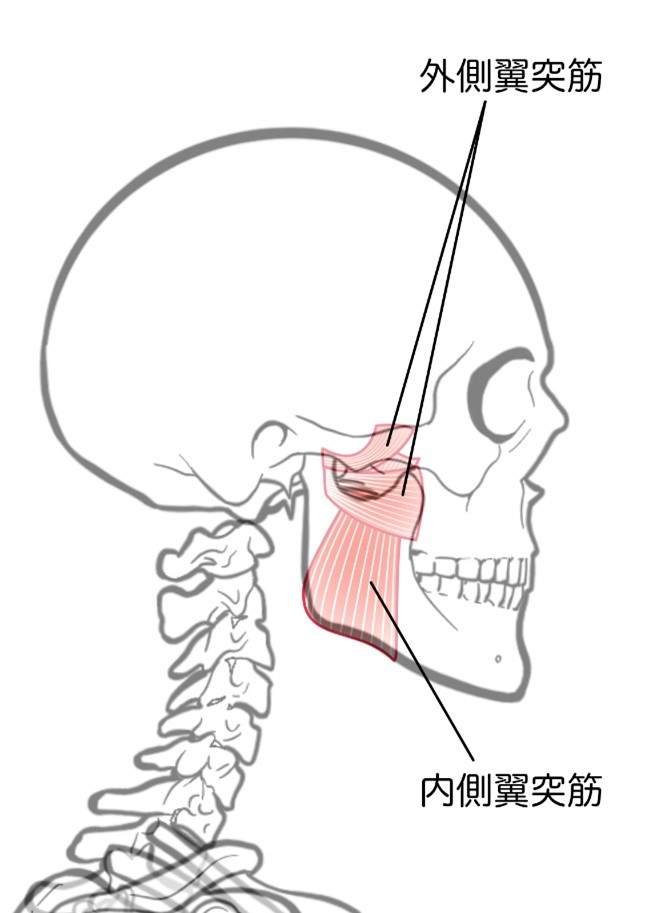

【外側翼突筋のマッサージ】

- 歯を噛みしめて、ひとさし指を両耳たぶ下の顎関節付近に置きます。

- 膨らんだ場所があります。その位置が「咬筋」と呼ばれる咀嚼筋です。

- 咬筋をひとさし指で押さえたまま口を口を開きます。

- 口を半開きにした状態で、咬筋の深層部にある外側翼突筋をゆっくりと人差し指でグリグリとほぐしていきます。

- 約1分間ゆっくりとほぐします。